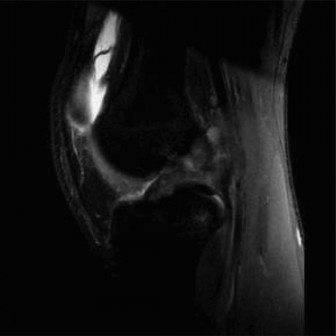

The patient then obtains the following radiograph (Fig. 10–22) which confirms the diagnosis of an OCD lesion of the medial femoral condyle. An MRI is then ordered to examine the lesion further. A T2 image is shown in Figure 10–23.

Figure 10–22

Figure 10–23

The correct answer is (C). The patient has an OCD lesion of the posterolateral aspect of the medial femoral condyle which is the most common location for these lesions. Pediatric patients have a much better prognosis for OCD lesions as open distal femoral physes are the best predictor of a successful outcome with nonoperative management. Lesions which have synovial fluid behind the lesion on MRI are potentially unstable and require much more aggressive surgical management to prevent detachment and separation. As this patient is young, has open distal femoral physes, and has no instability on MRI, a trial of conservative treatment is appropriate. Arthroscopic drilling (either antegrade or retrograde) can be performed for stable lesions which have not responded to a trial of conservative management (Fig. 10–24). Open reduction and internal fixation should be reserved for unstable lesions.